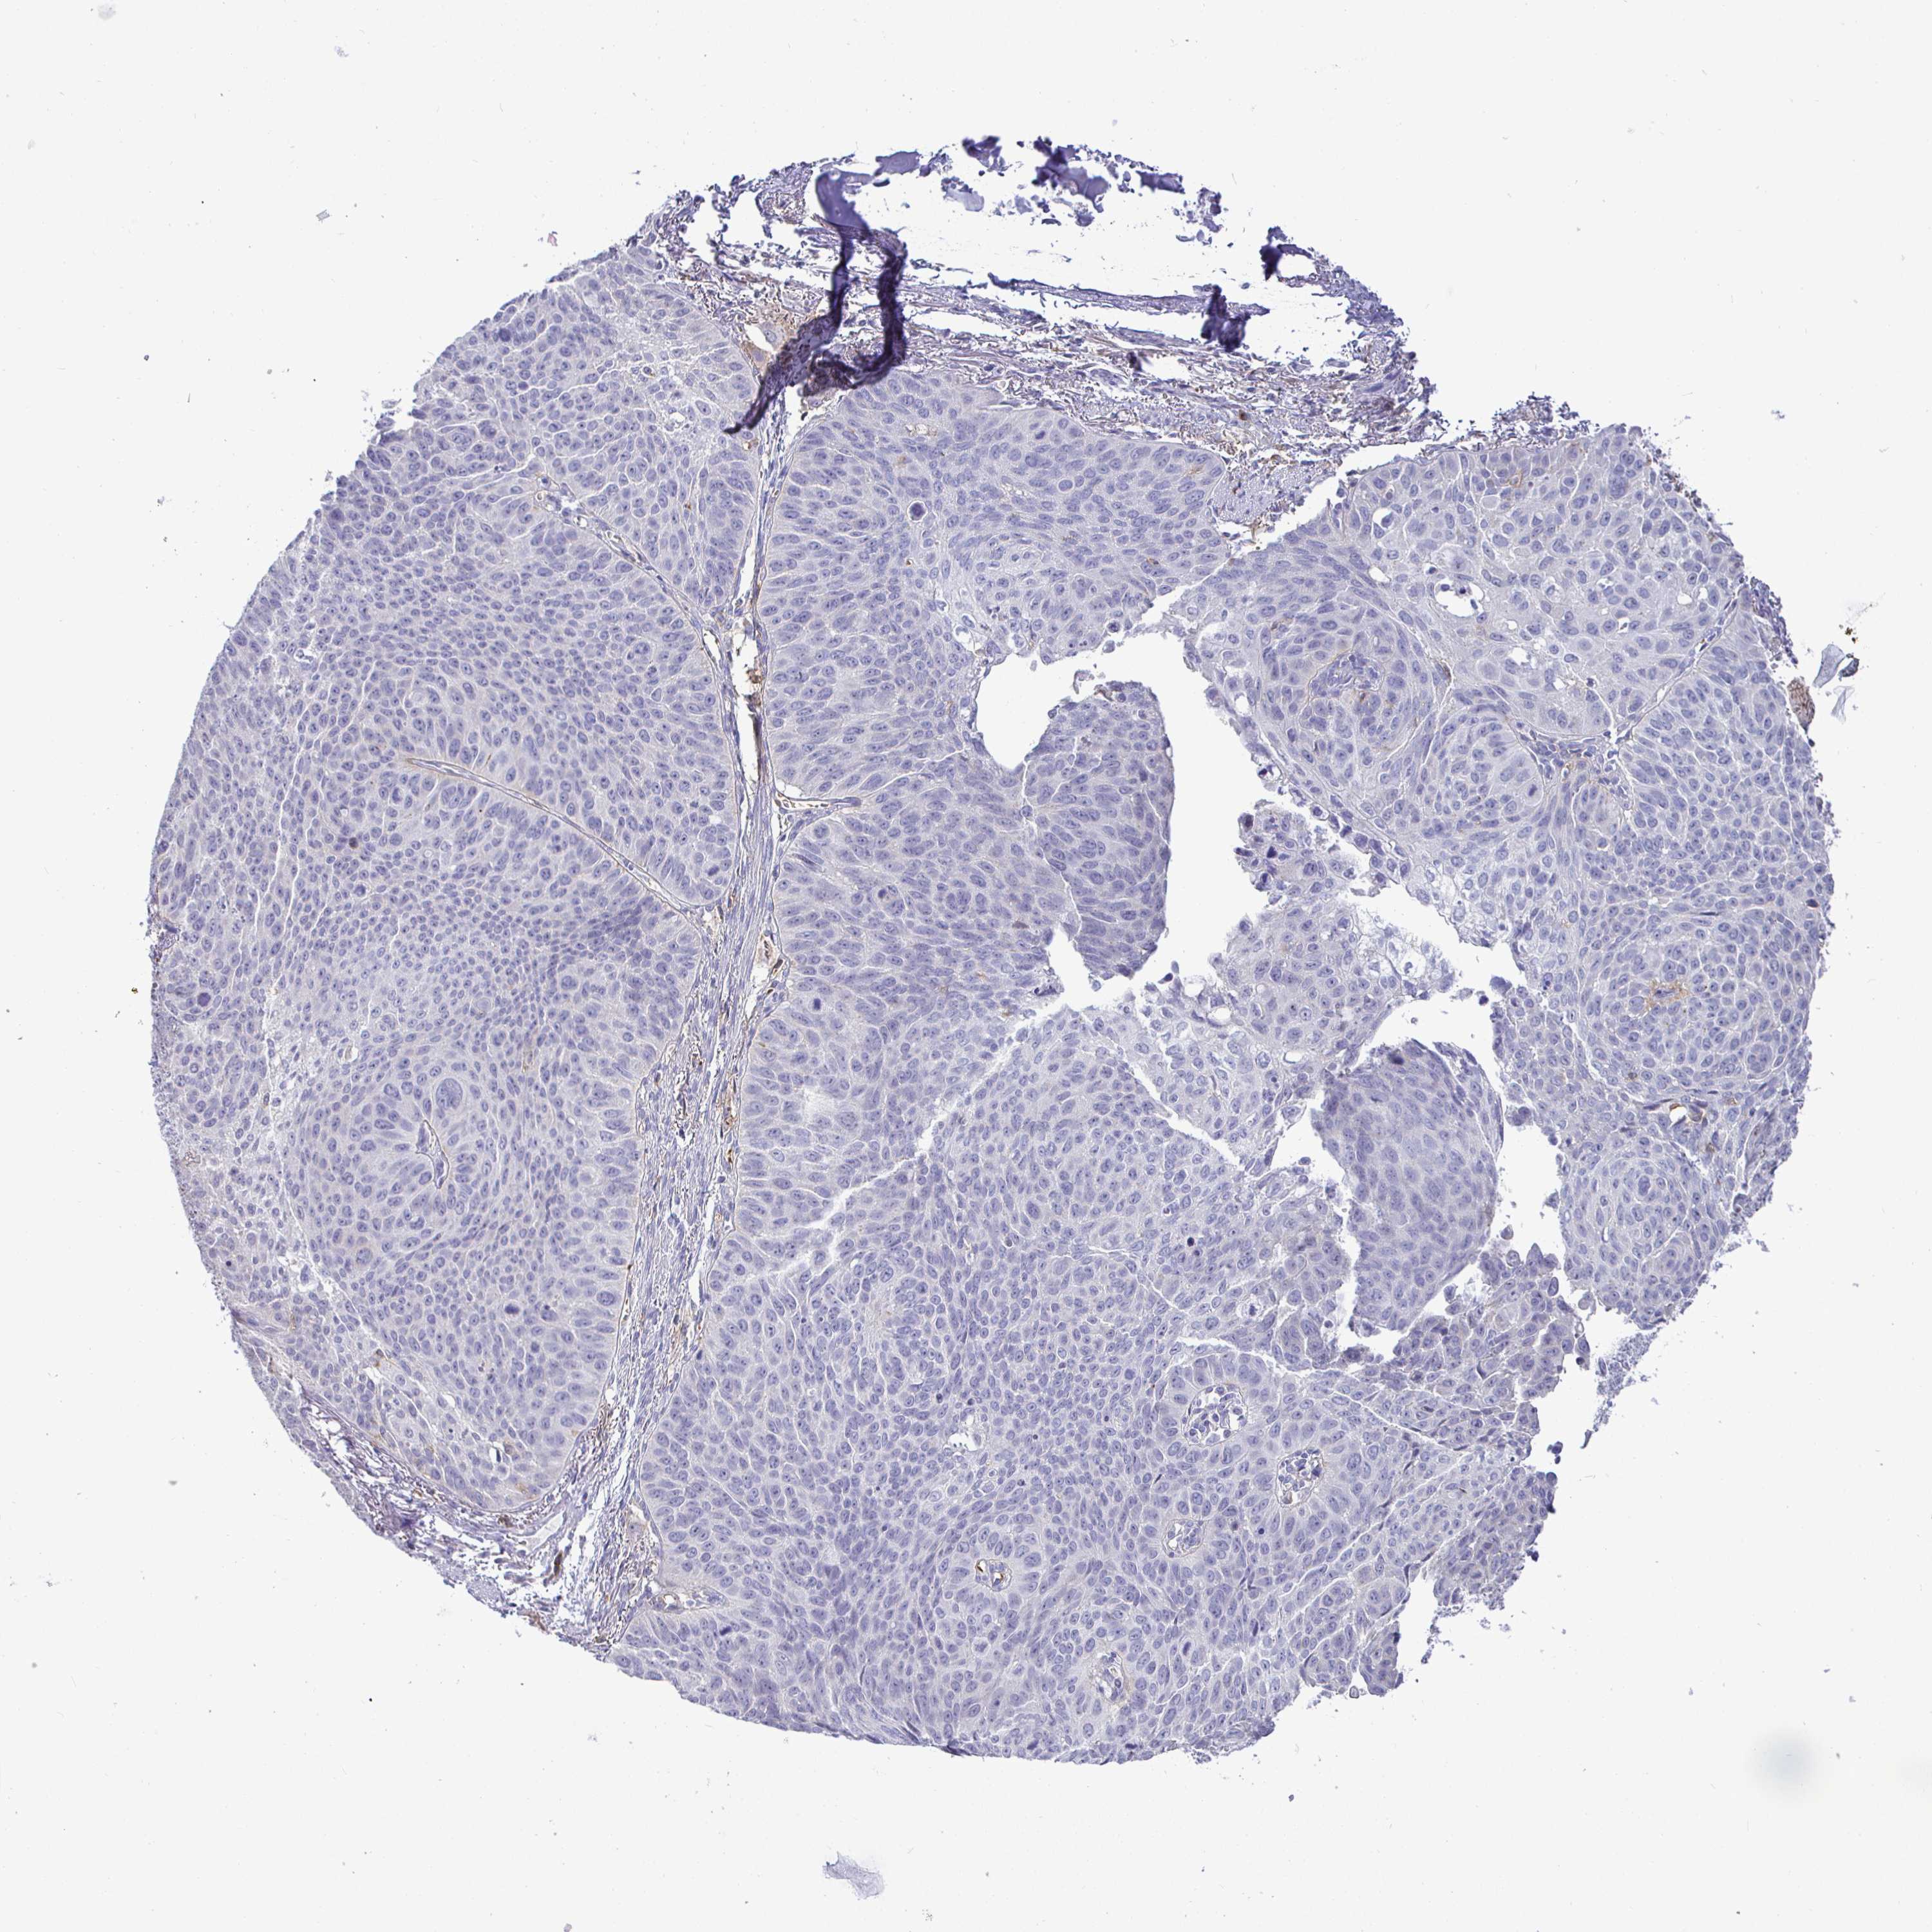

LUNG SQUAMOUS CELL CARCINOMA (TCGA) - Interactive survival scatter ploti

The Survival Scatter plot shows the clinical status (i.e. dead or alive) for all individuals in the patient cohort, based on the same data that underlies the corresponding Kaplan-Meier plots. Patients that are alive at last time for follow-up are shown in blue and patients who have died during the study are shown in red.

The x-axis shows the expression levels (FPKM) of the investigated gene in the tumor tissue at the time of diagnosis. The y-axis shows the follow-up time after diagnosis (years). Both axes are complimented with kernel density curves demonstrating the data density over the axes. The top density plot shows the expression levels (FPKM) distribution among dead (red) and alive patients (blue). The right density plot shows the data density of the survived years of dead patients with high and low expression levels respectively, stratified using the cutoff indicated by the vertical dashed line through the Survival Scatter plot. This cutoff is automatically defined based on the FPKM cutoff that minimizes the p-score. The cutoff can be changed by dragging the vertical line or by entering a cutoff value in the square labeled "Current cut-off".

Under the Survival Scatter plot the p-score landscape (black curve; left axis) is shown together with dead median separation (red curve; right axis). Dead median separation is the difference in median mRNA expression between patients who have died with high and low expression, respectively. It is calculated as follows: median FPKM expression of dead patients with high expression - median FPKM expression of dead patients with low expression. This is intended to aid the user in visually exploring custom cutoffs and the associated p-scores and dead median separation.

Individual patient data is displayed and can be filtered by clicking on one or more of the category buttons on the top of the page. Categories describing expression level and patient information include: high, low, alive, dead, female, male and tumor stages. The scale of the x-axis can be toggled between linear and log-scale by clicking on the "x log" button. Mouse-over function shows TCGA ID, patient information and mRNA expression (FPKM) for each patient.

& Survival analysisi

Kaplan-Meier plots summarize results from analysis of correlation between mRNA expression level and patient survival. Patients were divided based on level of expression into one of the two groups "low" (under cut off) or "high" (over cut off). X-axis shows time for survival (years) and y-axis shows the probability of survival, where 1.0 corresponds to 100 percent.

SIRPA is potential prognostic, high expression is unfavorable in Lung Squamous Cell Carcinoma (TCGA)

Best expression cut offi

Based on the FPKM value of each gene, patients were classified into two groups and association between prognosis (survival) and gene expression (FPKM) was examined. The best expression cut-off refers the FPKM value that yields maximal difference with regard to survival between the two groups at the lowest log-rank P-value. Best expression cut-off was selected based on survival analysis .

When clicking on this number, the vertical dashed line indicating cut-off, the interactive survival plot, and the Kaplan-Meier curve will be adjusted to show results based on the best expression cut-off.

: 33.8

P scorei

Log-rank P value for Kaplan-Meier plot showing results from analysis of correlation between mRNA expression level and patient survival.

N/A

5-year survival highi

5-year survival for patients with higher expression than the expression cutoff.

For melanoma and glioma, 3-year survival is shown.

5-year survival lowi

5-year survival for patients with lower expression than the expression cutoff.

TCGA RNA samplesi

RNA-seq data is reported as average FPKM (number Fragments Per Kilobase of exon per Million reads), generated by the The Cancer Genome Atlas (TCGA) .

Normal distribution across the dataset is visualized with box plots, shown as median and 25th and 75th percentiles. Points are displayed as outliers if they are above or below 1.5 times the interquartile range. FPKM values of the individual samples are presented next to the box plot.

Average pTPM 29.4

Number of samples 489